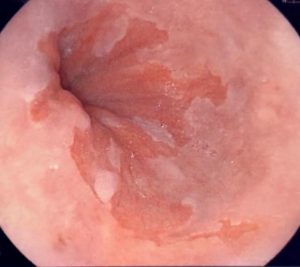

El esófago de Barrett (BE, por sus siglas en inglés) es un trastorno por el cual el revestimiento del esófago presenta daño a causa del ácido gástrico. El esófago también es conocido como el conducto alimenticio y conecta la garganta con el estómago.

Las personas con BE tienen un mayor riesgo de padecer cáncer en la zona comprometida.